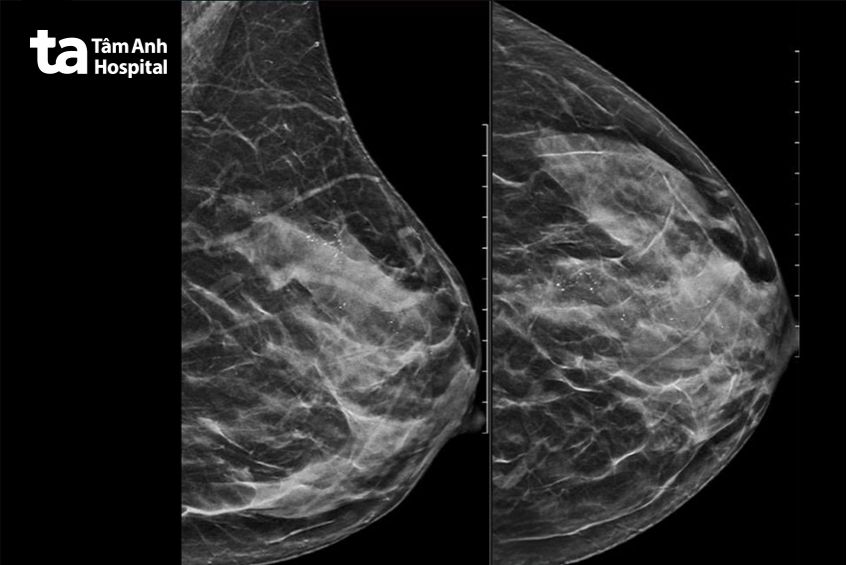

Theo bác sĩ Huỳnh Bá Tấn, khoa Ngoại Vú – Đầu Mặt Cổ, xét nghiệm cho thấy chị Hồng mắc đồng thời ung thư vú giai đoạn tại chỗ và ung thư tuyến giáp dạng nhú. Kết quả siêu âm và nhũ ảnh ghi nhận chị Hồng có khối u khoảng 5 cm ở vú trái, có tổn thương BIRADS 4B – mức độ nghi ngờ ác tính cao, sinh thiết lõi kim khẳng định ung thư biểu mô ống tại chỗ. Siêu âm tuyến giáp phát hiện nhân ở thùy phải, nghi ngờ ác tính. Kết quả chọc hút kim nhỏ (FNA) cho thấy ung thư tuyến giáp dạng nhú. Ngoài ra, bệnh nhân còn được phát hiện đa nhân giáp hai thùy.